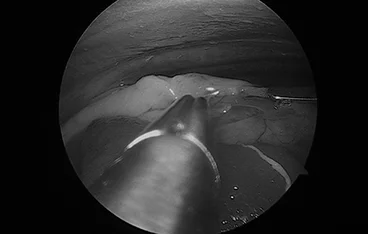

C-arm 투시 영상장비를 이용해 심장 내부에 기생하는 사상충을 정밀하게 제거합니다

6. 유미흉 및 기관 질환 진단·치료

가슴 속에 액체가 차는 유미흉, 기관허탈 등 호흡기 문제를 내시경 장비로 진단하고 최소침습적으로 치료합니다.